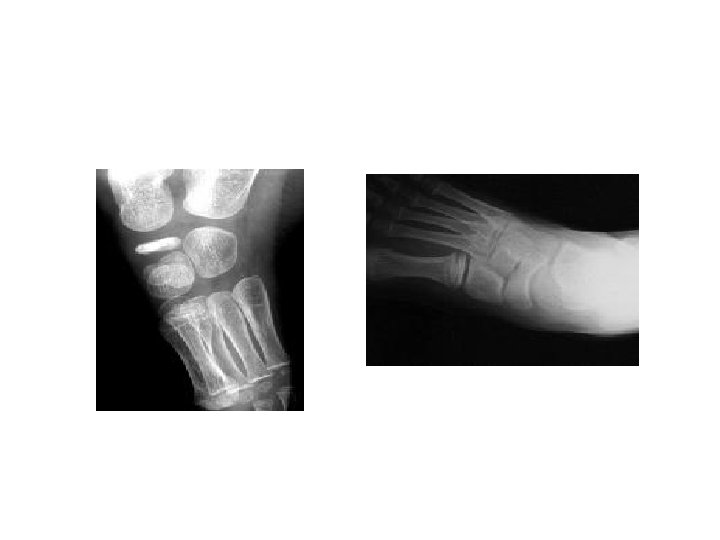

Crushing Osteochondritis it's characterized by spontaneous necrosis of the ossific nucleus in long bone epiphesis or one of the cuboidal bones of the wrist or foot. The pathological changes are the same as those in other forms of osteonecrosis : bone death, fragmentation or distortion of the necrotic segment and reactive new bone formation around the ischemic trabeculae. Clinical features : Pain and limitation of joint movement are the usual complaints. Tenderness is sharply localized to the affected bone. X-rays show the characteristic increased density, accompanied in the later stages by distortion and collapse of the necrotic segment. Examples of crushing Osteochondritis are Freiberg's diseases of the metatarsal ; Kohler's disease of the navicular ; Kienbock's disease of the carpal lunate ; Panner's disease of the capitulum and Scheuermann's disease (vertebral Osteochondritis ). Treatment is conservative(analgesia and splintage) rarely need operation. •